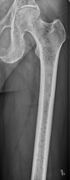

The diagnostic examination of a person with suspected multiple myeloma typically includes a skeletal survey. This is a series of X-rays of the skull, axial skeleton, and proximal long bones. Myeloma activity sometimes appears as "lytic lesions" (with local disappearance of normal bone due to resorption) or as "punched-out lesions" on the skull X-ray ("raindrop skull"). Lesions may also be sclerotic, which is seen as radiodense.[70] Overall, the radiodensity of myeloma is between −30 and 120 Hounsfield units (HU).[71] Magnetic resonance imaging is more sensitive than simple X-rays in the detection of lytic lesions, and may supersede a skeletal survey, especially when vertebral disease is suspected. Occasionally, a CT scan is performed to measure the size of soft-tissue plasmacytomas. Nuclear Medicine Bone scans are typically not of any additional value in the workup of people with myeloma (no new bone formation; lytic lesions not well visualized on nuclear bone scan).

X-ray of the forearm, with lytic lesions

Multiple myeloma in the upper arm

Femur with multiple myeloma lesions

Same femur before myeloma lesions for comparison